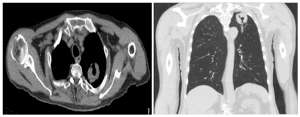

A 67-year-old immunocompetent male with a past medical history significant for hypertension (on lisinopril 20 mg daily), controlled type 2 diabetes (on sitagliptin 100 mg daily, glipizide 10 mg twice a day, and Jardiance 12.5 mg-metformin 1000 mg combination pill twice a day), chronic obstructive pulmonary disease (COPD) (on albuterol, fluticasone propionate-salmeterol and tiotropium inhalers), and tobacco use disorder with a 30-pack year smoking history presented for a routine physical exam. Review of systems was within normal limits. On physical examination, his lungs were clear to auscultation and percussion without any wheezing or gallops. He did not have any remarkable head, ear, nose, throat, cardiac, gastrointestinal, neurological, or musculoskeletal findings. He had a low-dose chest CT performed for the purposes of lung cancer screening, which was significant for a large mass lesion with central cavitation in the posterior left lung apex measuring 4.5 cm, increased in size from previous, with mild adjacent surrounding inflammatory bronchiolitis also in the left lung apex.

Figure 1: a) T2-weighted axial image with a large mass lesion with central cavitation in the posterior left lung ape

b) T2-weighted coronal image with a large mass lesion with central cavitation in the posterior left lung apex